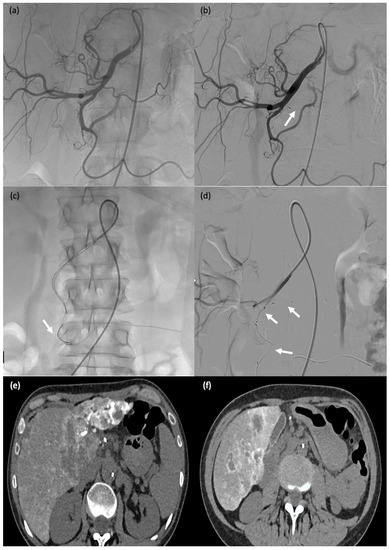

Figure 4. A 75-year-old male patient (#29) on dialysis for chronic kidney disease with dysfunction of the arteriovenous fistula. (a) Post-anastomosis venous thrombosis (arrow): the patient was taken to the operating room for thrombectomy. (b,c) Thromboaspiration and angioplasty (arrows). (d) MVP-5Q implantation to occlude collateral venous circulation, thereby redistributing the blood flow (arrow).